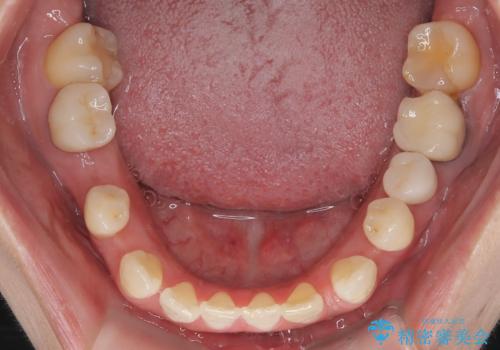

- 歯と歯の間に大きなスペースがある「空隙歯列(すきっ歯)」と、一部の歯が欠損していることによる噛み合わせの不安定さを主訴にご来院されました。

精密検査の結果、全体の隙間を閉じるだけでは適切な咬合バランスが得られないため、まずはインビザラインを用いて歯の位置を理想的な場所へと整える計画を立案しました。矯正によって欠損部位に適切なスペースを確保した後、その部分にインプラントを埋入することで、審美性と機能性の両立を目指しました。

矯正によって土台となる歯列が整った段階で、欠損部位へインプラントを埋入しました。これにより、周囲の歯を削ることなく、天然歯のような噛み心地を再現することができました。